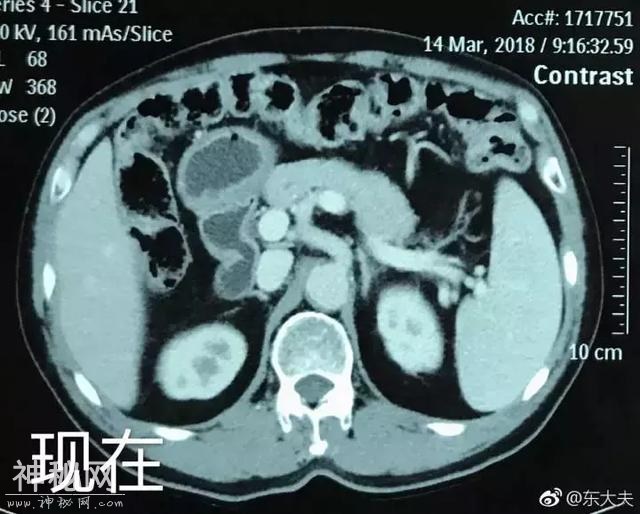

△图中阴影部分为肿瘤

△肿瘤逐渐变小

令人惊喜的是,在三个月的四次化疗、对病灶做局部放疗以及两个巩固周期的治疗后,患者的肝转移灶和原发灶癌竟然奇迹般的消失了,并且在之后的一年里癌细胞没再发生新的进展,现在患者已经回到老家,正常上班了。

△肿瘤几乎消失

△箭头处为癌细胞消失后留下的疤